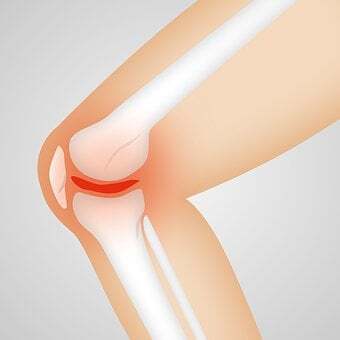

류마티스 관절염은 면역체계에 이상이 생겨 관절에 염증이나 부종등 심한 통증을 수반하게 되는데요. 연골과 뼈가 손상을입어 관절이 변형되고 관절의 기능이 저하되는 질환이라 할수 있습니다.

관절의 안쪽을 싸고있는 활막에 자주 염증이 쌓이게되면, 활막이 증가하고 주변 조직들을 파괴하는 것입니다. 전국에 대략 70 ~ 80 만명으로 추정되며, 특히 여성분들에게 많이 발병되고, 연령은 30 대 ~ 50 대가 피크라 할수 있습니다.

류마티스 관절염은 그 면역체계에 이상이 생겨 자신의 세포나 몸을 공격하고, 관절에 염증을 일으키는 것이라 할수 있습니다. 본래는 관절액을 만들고 관절의 기능을 지원하는 미끄럼 막에 염증이 생기고, 염증이 장기화되면서 관절의 파괴로 이어지게 됩니다.

손이나 발가락 같은 작은 관절에 발병하는 경우가 많다고 볼수 있지만, 기간이 길어지면서 무릎이나 어깨ㆍ허리 등의 큰 관절에 염증이 전이되는 경우가 대부분입니다. 아직까지 왜 이런 증상들이 일어나는지 완벽하게 밝혀지지는 않았지만, 유전 적 요인과 흡연 습관, 잇몸 질환과 관련이 있다고 보고되고 있습니다.